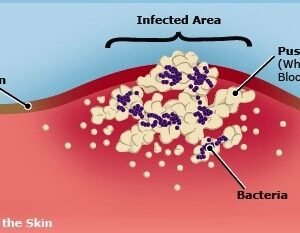

Abscess / Carbuncle / Boils